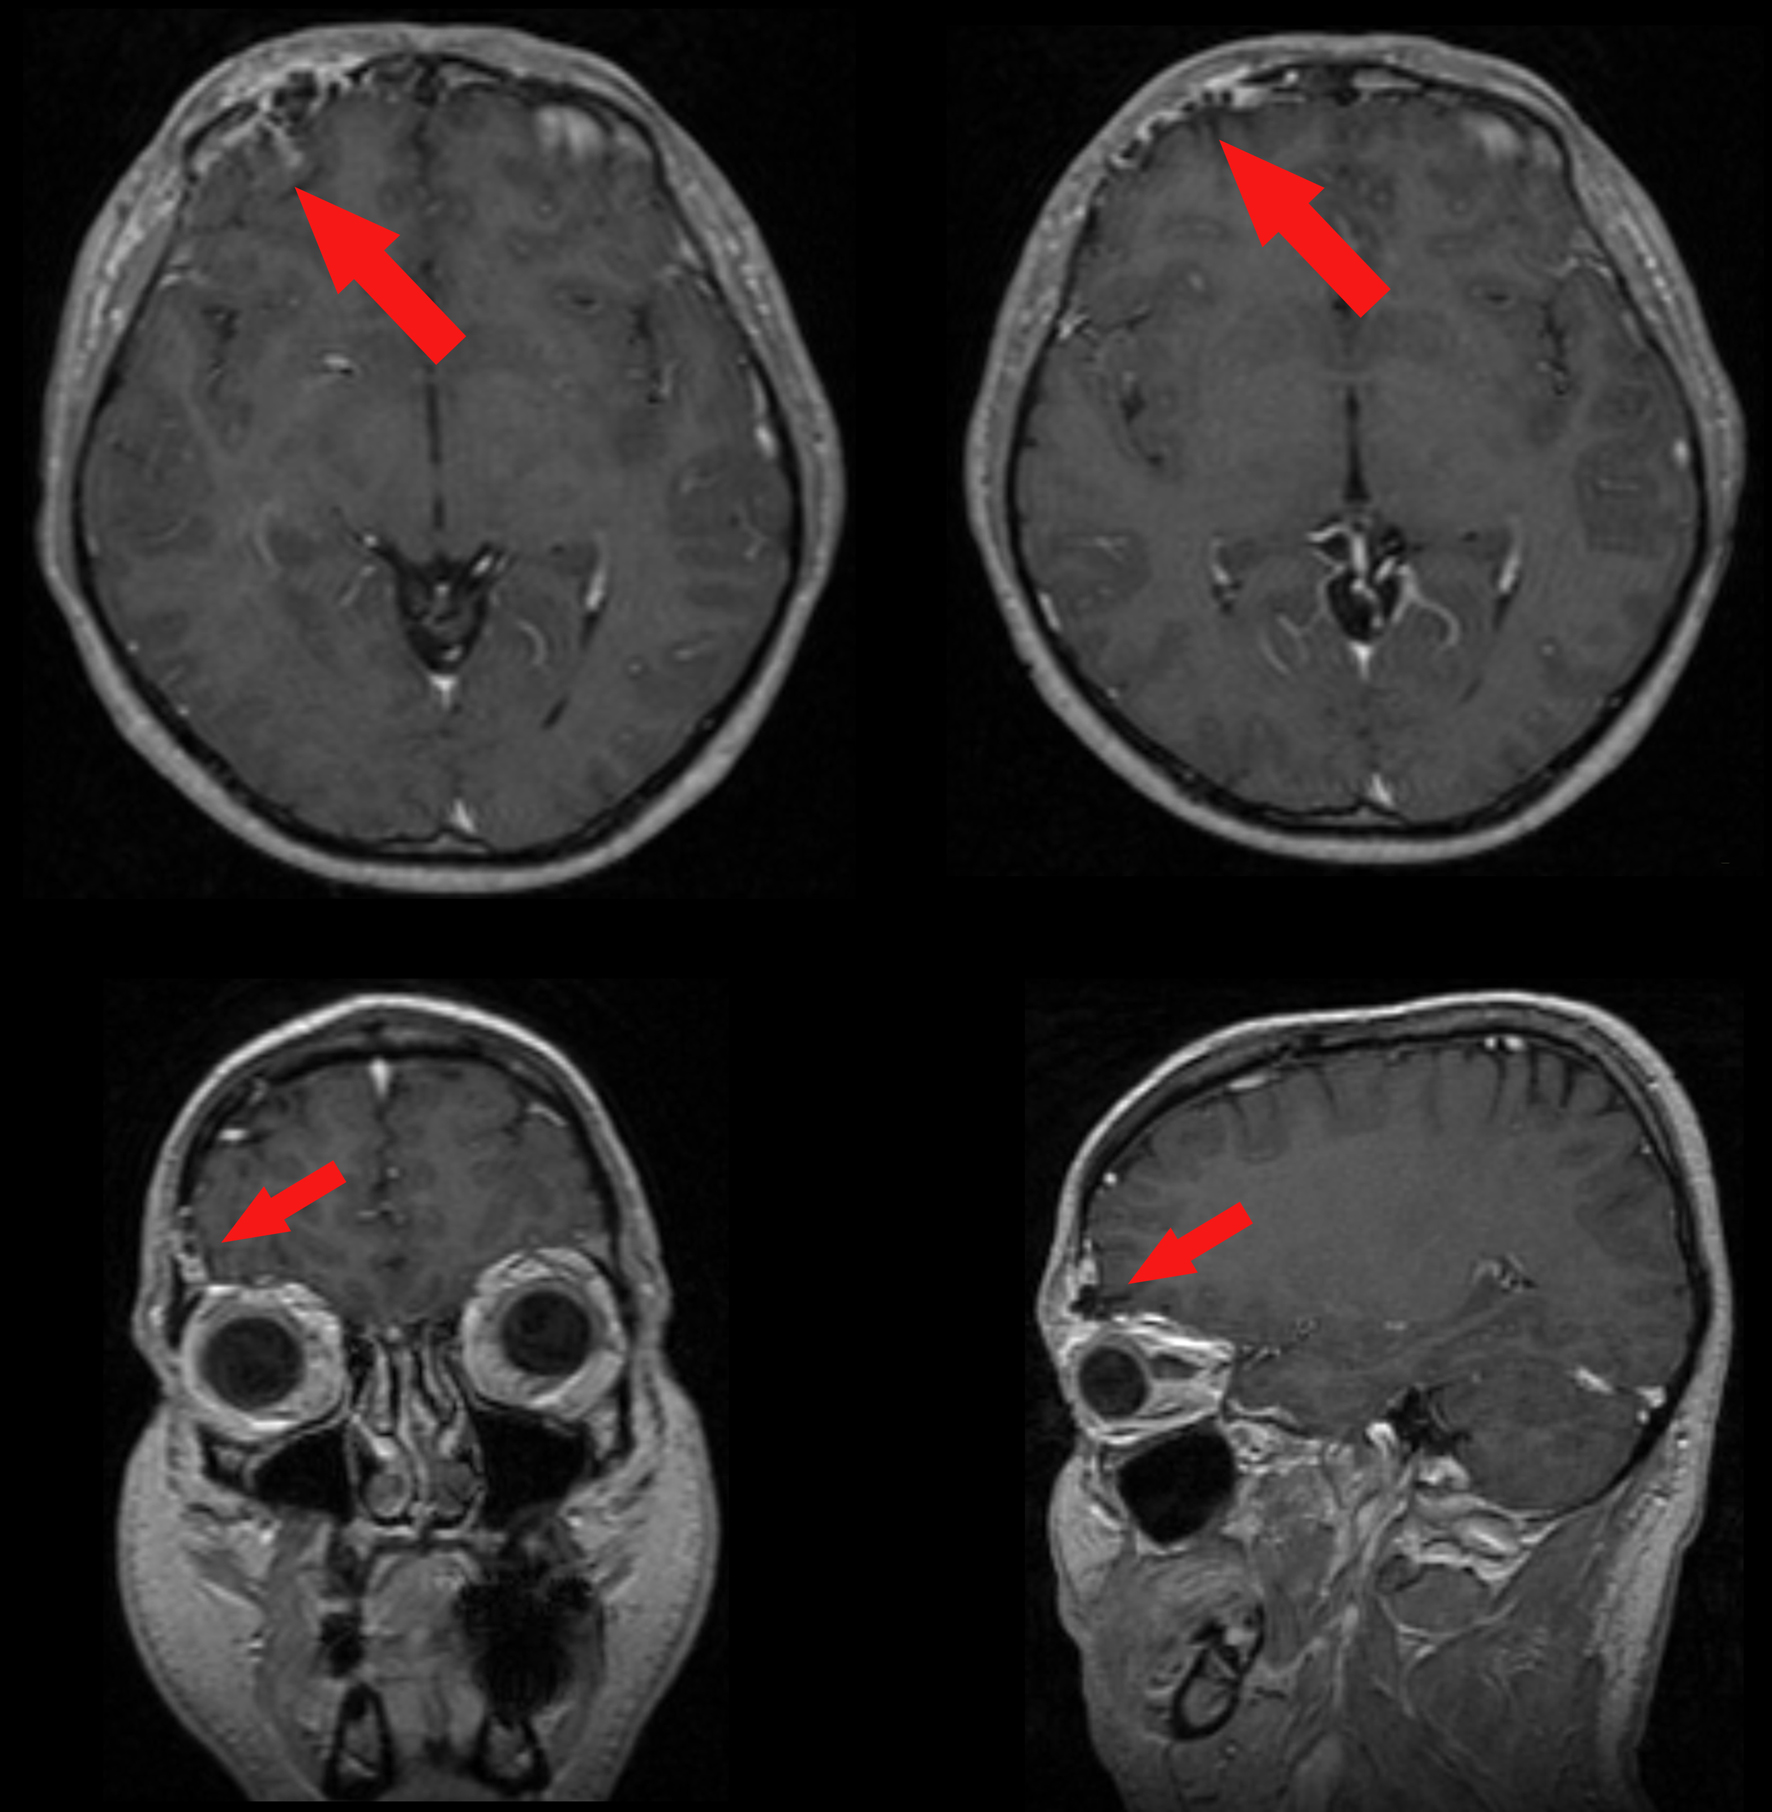

A 37-year-old man was admitted to our hospital complaining of frequent episodes of headache for the past several months. He was followed by the otolaryngologist for sinusitis, but for the persistence of the headache, computed tomography (CT) and magnetic resonance (MR) of the brain were performed. CT scans showed a right frontal calcified lesion e (Fig. 1) and marked enhancement post contrast and MR revealed hypointense lesion in the right frontal lobe with heterogeneous contrast enhancement after Gadolinium administration (Fig. 2). On admission to our department, general, physical and neurological examination found no abnormalities. X-ray scan of the skull revealed an extended geographical area of osteolysis in charge of the frontal squama in the right supraorbital region with involvement of the roof of the ipsilateral orbit and hypoplasia of frontal sinus. A brain CT and MR were repeated and showed no changes beyond those already performed. There were no stigmata or family history of neurofibromatosis.

![]() Click for large image | Figure 2. Pre-operative enhanced MR showing the meningioangiomatosis (red arrows) in the 3-plains projection. |